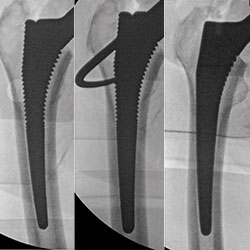

Intraoperative fluoroscopy: assessing acetabular component positioning

Intraoperative fluoroscopy: optimizing femoral sizing and filling of the femoral canal